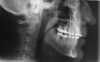

Fig 11. Pretreatment lateral (Fig 11) and posteroanterior (Fig 12) cephalometric x-rays, along with a lateral overjet image (Fig 13). Maxillary deficiency was present in the transverse and sagittal planes.

Figure 11

Fig 12. Pretreatment lateral (Fig 11) and posteroanterior (Fig 12) cephalometric x-rays, along with a lateral overjet image (Fig 13). Maxillary deficiency was present in the transverse and sagittal planes.

Figure 12

Fig 13. Pretreatment lateral (Fig 11) and posteroanterior (Fig 12) cephalometric x-rays, along with a lateral overjet image (Fig 13). Maxillary deficiency was present in the transverse and sagittal planes.

Figure 13